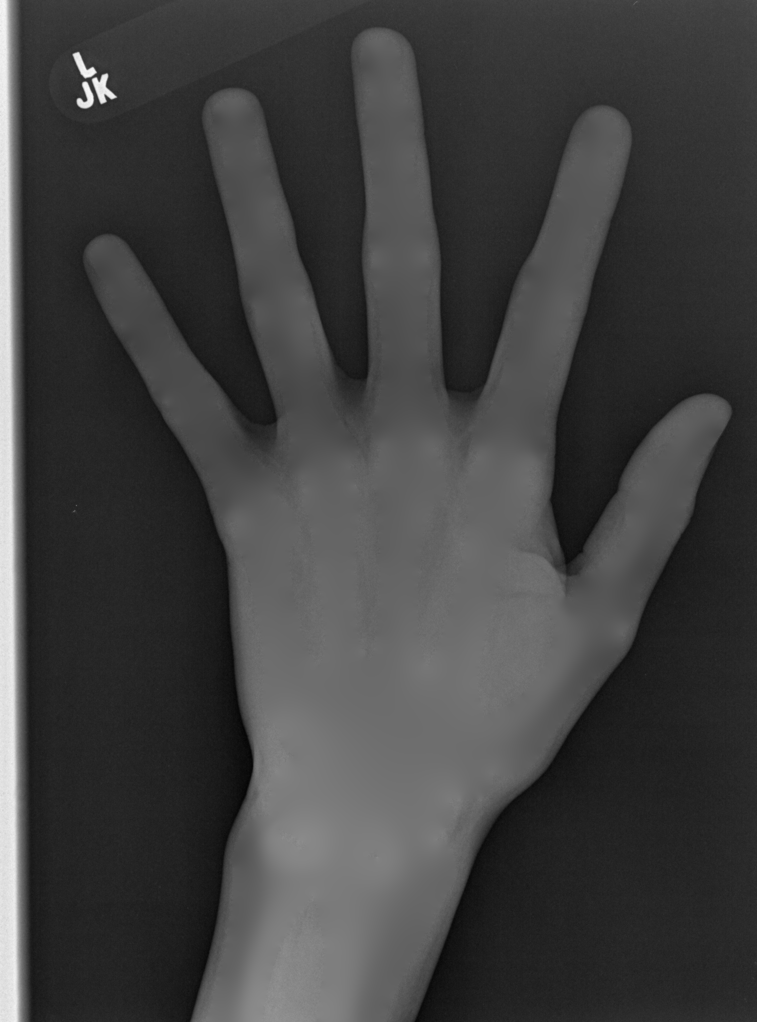

We performed three experiments for our method. First, we perform our method on several X-ray images, showing our method is not restricted by specific imaging objects. Second, we compared our method with image enhancement method and dehazing method, showing that our modification of the original dehazing indeed helps in this task. Third, we perform our method on a hand X-ray image dataset, showing its effectiveness and efficiency.

Several results from our method are shown in Fig. 7. The left column is the original input image. The right two columns are the soft tissue and bone image, respectively. It can be told that the soft tissue image is smooth as we assumed. Meanwhile, the bone image has better image contrast as desired. Moreover, our method can reach real-time performance on these X-ray images. The running time of our method on these images is reported in Table I.

In the third experiment, we applied our method on a hand X-ray image data set (RSNA), which contains more than 10,000 hand X-ray images. And the image has high resolution (usually larger than ). These images are collected from clinical applications. Therefore, we can apply our method on these practical images, showing the efficiency and effectiveness of our method on real high resolution images.

In each panel of Fig. 10, the input image (left) is decomposed into soft tissue (middle) and bone image (right) by our method. Although we only show the first ten images from the data set, the results for the rest images are similar.

The bone images have better image contrast since the parameter is theoretically guaranteed. Such enhancement can also be directly told by radiologists. Such enhancement is good for bone diagnosis in practical applications.